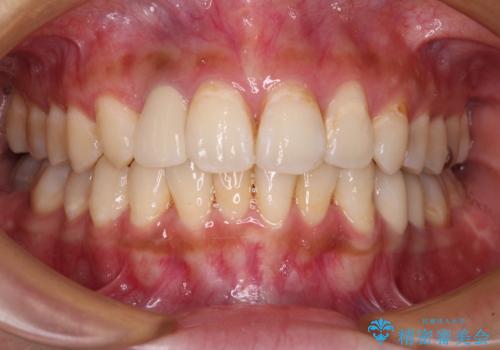

以前治療した前歯をきれいに治したい オールセラミッククラウン

- 根管治療はやり直さずに、ファイバーポストを使用した土台を植立して、オールセラミッククラウンにて補綴することとしました。

神経を取り除いた歯の変色は、クリーニングやホワイトニングでは改善できないため、オールセラミッククラウンなどによる補綴治療が必要となります。